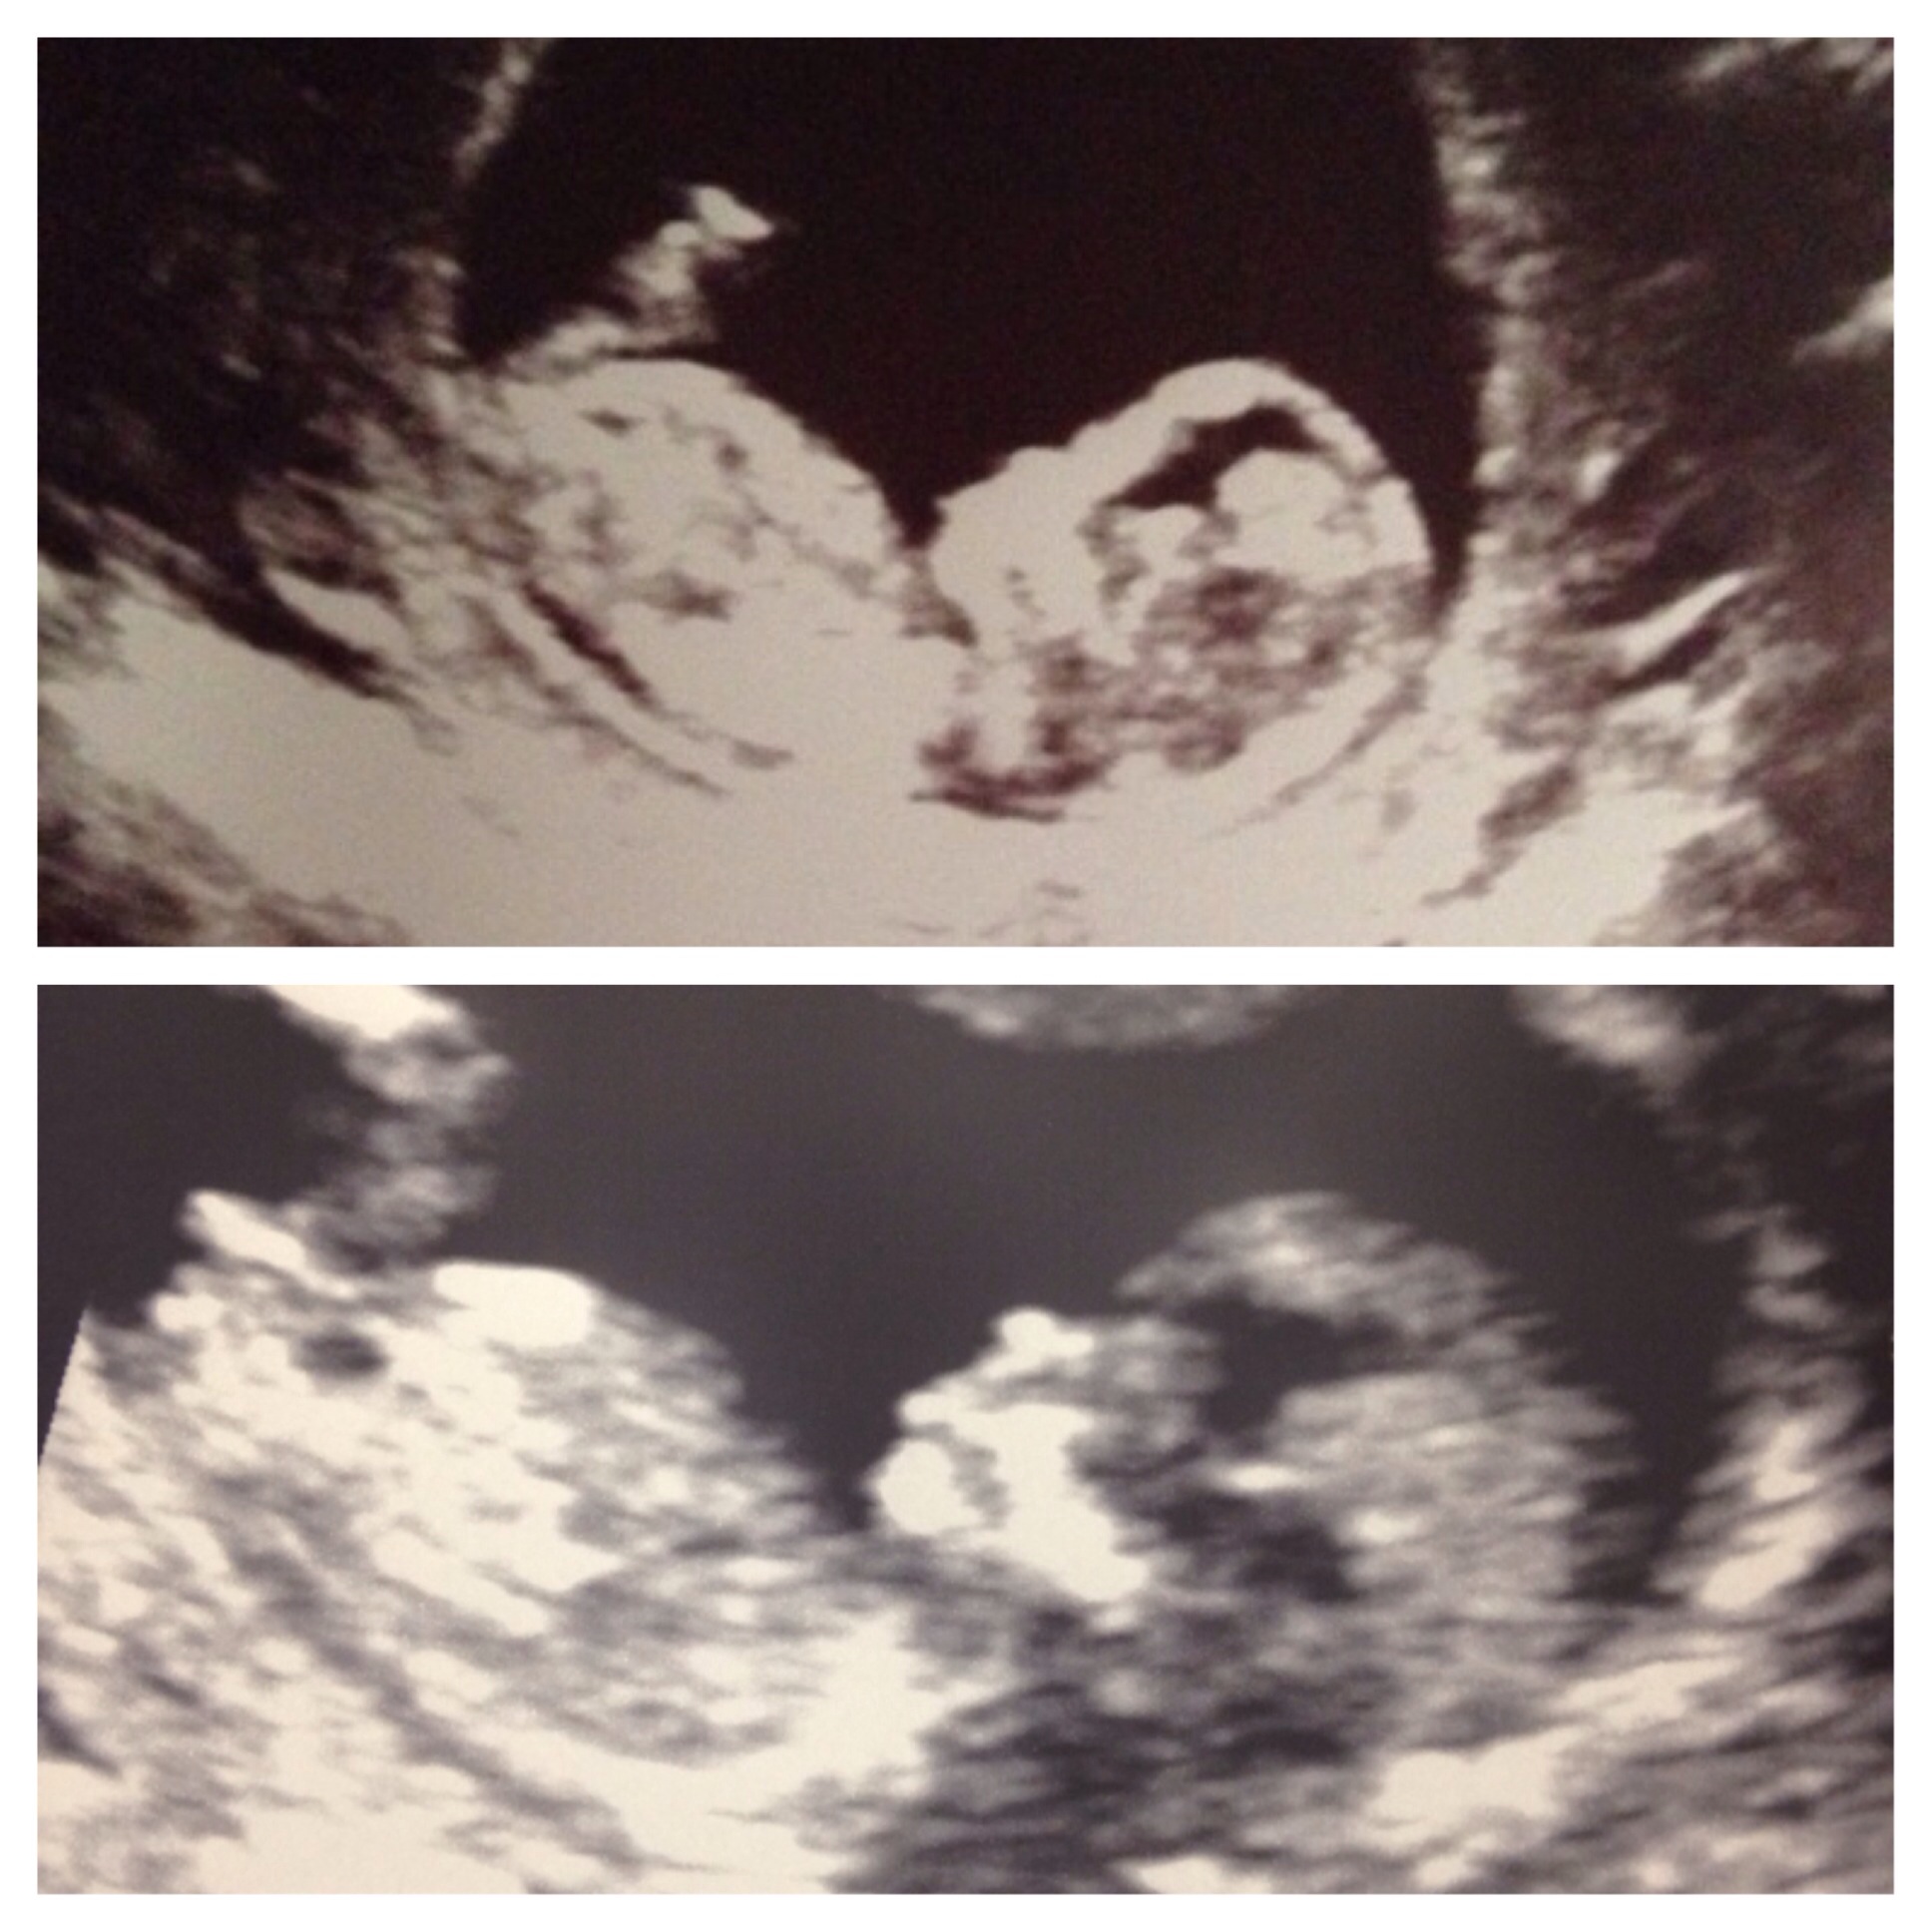

12 weeks 3 days, heartrate 165, in second picture umbilical cord is between the legs, any gender guesses! :) Attachment 20519

It's a bit early, but I'll cautiously guess girl :)

It's early but I am guessing girl because of the nub angle.